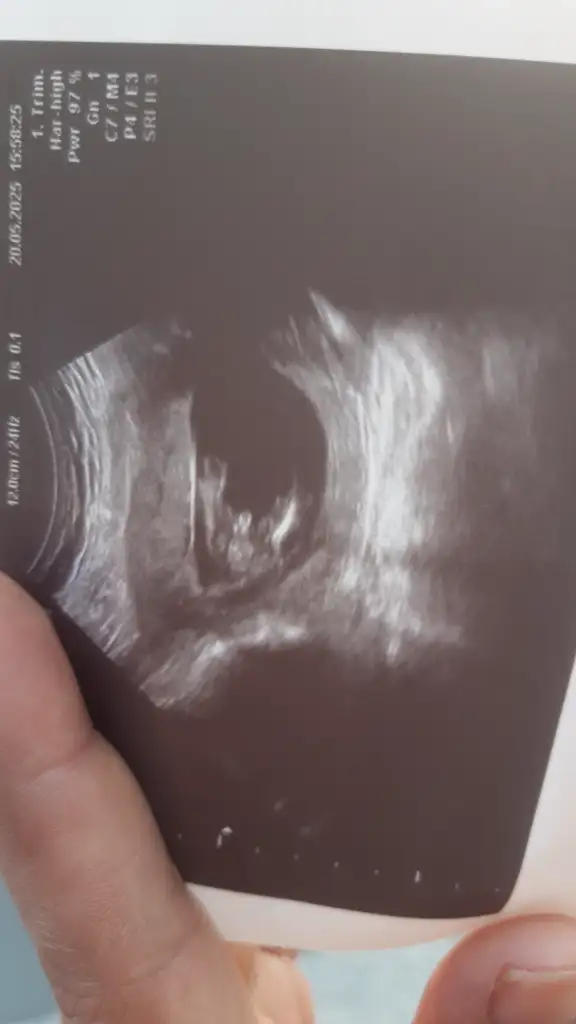

Kizlar sizce 13+5 günlük

Eklentiler

• IMG-20250520-WA0002.webp

IMG-20250520-WA0002.webp

12,4 KB · Görüntüleme: 35

• 17477520189021923888813847793324.webp

17477520189021923888813847793324.webp

18 KB · Görüntüleme: 28